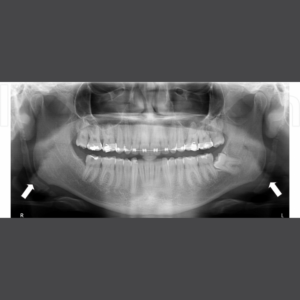

1. Chụp phim Panorama 2D là gì?

Chụp phim Panorama 2D (X-quang toàn cảnh) là kỹ thuật chẩn đoán hình ảnh giúp bác sĩ xem được toàn bộ cấu trúc răng – xương hàm – khớp thái dương hàm – xoang chỉ trên một tấm phim duy nhất.

Khác với các loại phim cục bộ, Panorama cho cái nhìn rộng và trực quan, giúp đánh giá tổng thể sức khỏe răng miệng, từ đó lập kế hoạch điều trị chính xác và hạn chế tối đa sai sót trong quá trình chăm sóc.

Những trường hợp nào cần chụp 2D Panorama?